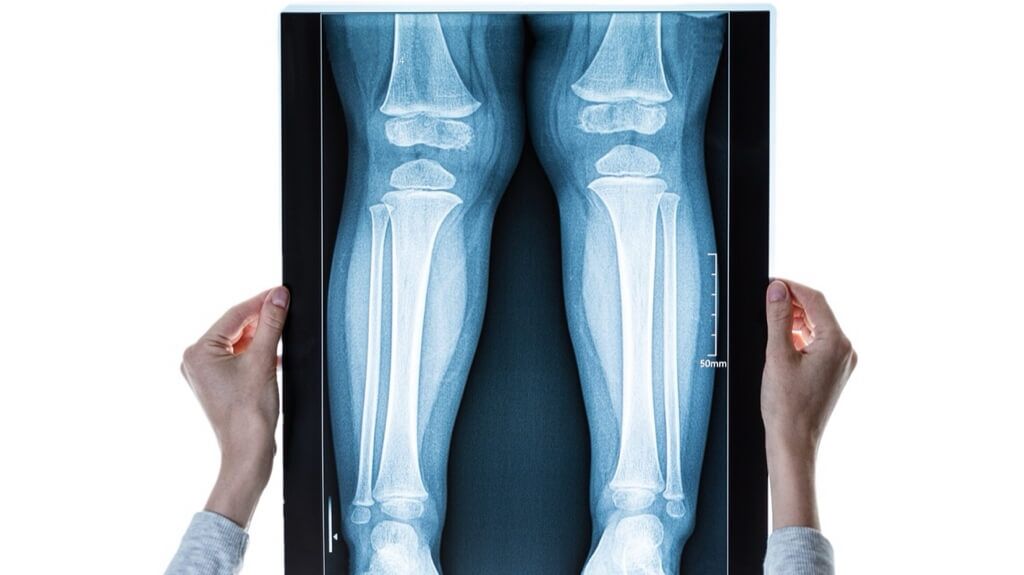

- All pre-operative consultations and tests (X-rays, blood work)

- The surgery itself, including the cost of the internal nails or external fixators